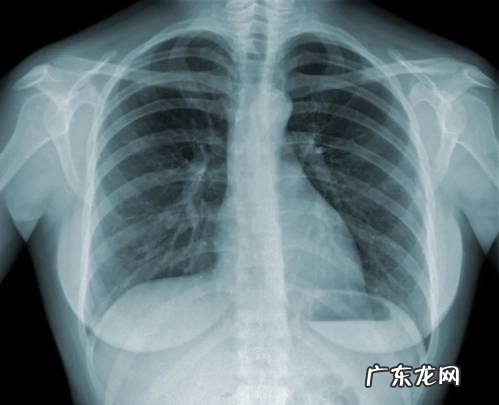

一般来说,肺结节指的是影像(CT/胸片检查)上看到的各种边缘清楚或模糊、直径≤3cm的肺部阴影 。

当我们发现检查出肺结节时,首先应保持冷静 。这里教大家通过结节的大小与形状,来初步判断肺结节的良、恶性 。

二看形状:

良性结节主要表现为:圆形、类圆形、椭圆形 。恶性肺结节的形状就比较“古怪“,形状越古怪,恶性的可能性越大 。所谓古怪的形状有分叶、毛刺、胸膜牵拉、含气细支气管征和小泡征、偏心厚壁空洞等 。